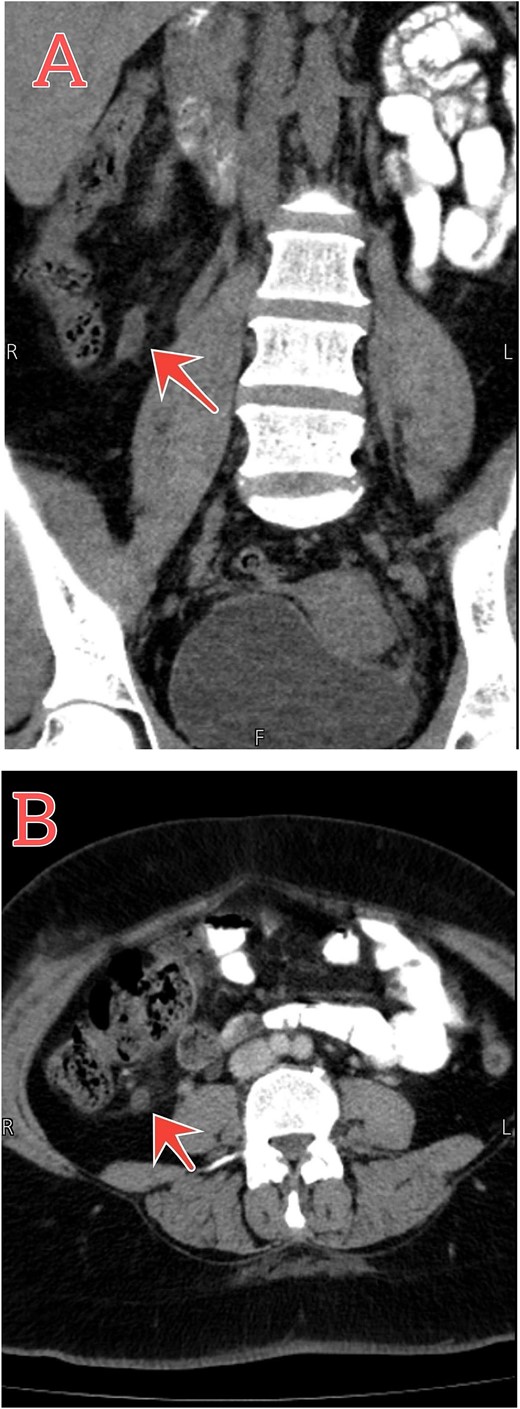

The patient was treated conservatively for two days by giving IV cefuroxime 1.5 mg three times per day, metronidazole 500 mg three times per day, pantoprazole 40 mg once daily, and acetaminophen 1 mg four times per day. Follow-up CT scan showed resolution of the condition (Fig. 2). She was discharged back home with good general conditions without complications.

Follow-up abdomen–pelvic CT scan. (A and B) Coronal and axial sections show resolution of the inflammatory process postconservative management (red arrows).